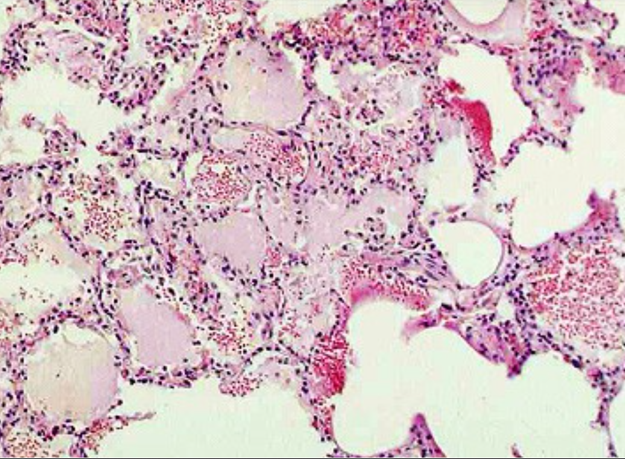

(2)镜下,受累的细支气管壁充血水肿,嗜中性粒细胞浸润,粘膜上皮细胞坏死脱落,管腔内充满大量嗜中性粒细胞、浆液、脓细胞、脱落崩解的粘膜上皮细胞。支气管周围受累的肺泡壁毛细血管扩张充血,肺泡腔内见嗜中性粒细胞、脓细胞、脱落的肺泡上皮细胞,尚可见少量红细胞和纤维素。病灶周围肺组织呈不同程度的代偿性肺气肿和肺不张。肺组织内各病灶可呈炎症的不同发展阶段,病变不一致,早期主要表现为炎性充血水肿,浆液性渗出;有些病灶表现为细支气管炎及细支气管周围炎;有些则呈化脓性病变,支气管及肺泡壁遭破坏。